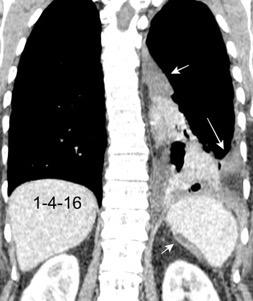

Colecciones “inflamatorias” abdominales llegan al tórax vía el hiato esofágico o por vía transdiafragmática

Afectación transdiafragmática: 5,6-43,7% de quistes hepáticos. “Área desnuda” del hígado.

Panda A et al. “Straddling Across Boundaries”. Thoracoabdominal Lesions: Spectrum and Pattern Approach. Curr Probl Diagn Radiol. 2015 Área desnuda. El hígado en contacto directo con el tendón central del diafragma. Contiene el hiato de VCI.